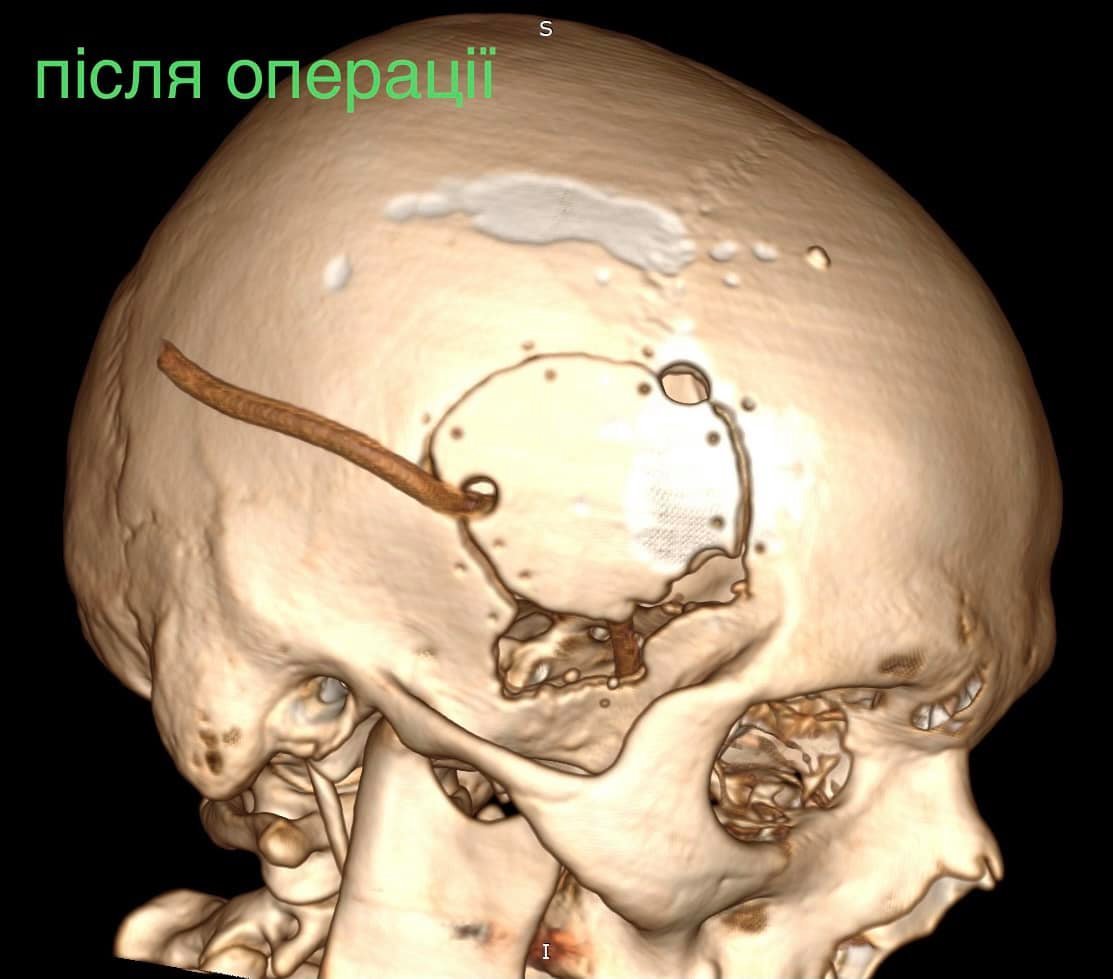

Як повідомив у Фейсбуці нейрохірург дитячої лікарні Михайло Ловга, у хлопця була куля в голові, що призвела до руйнації скроневої кістки та частини головного мозку.

«Ми виконали невідкладну операцію і вилучили стороннє тіло, видалили пошкоджені тканини і відновили цілісність збережених тканин. Добре, що куля зупинилась в 1 см від надзвичайно важливої судини і права скронева частка (яка пошкодилась в результаті травми) – функціонально незначима. Інакше, наш козак був би зовсім іншим, назавжди», – написав Михайло Ловга.